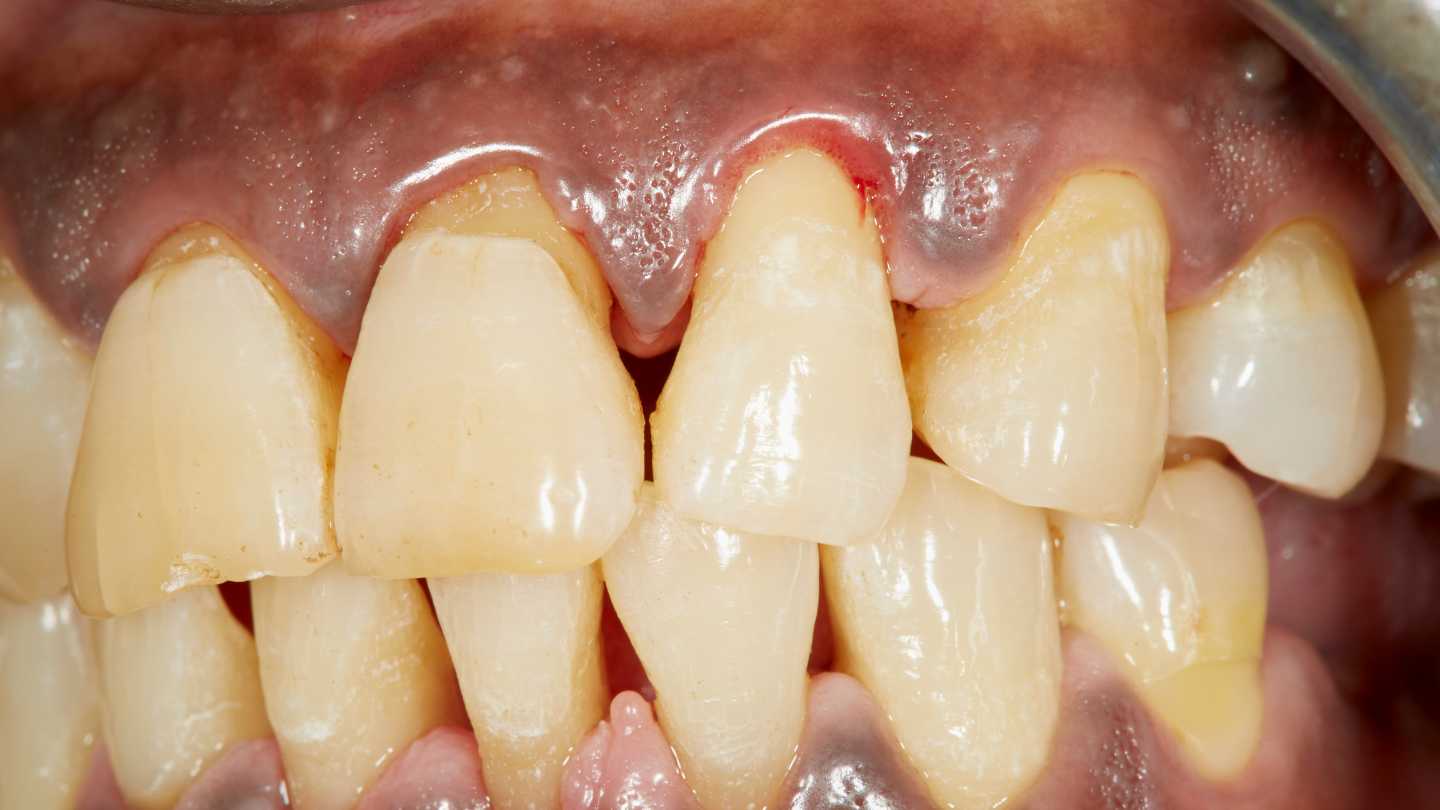

Principalele simptome ale gingivitei includ gingii rosii, umflate si sensibile, care pot sangera usor in timpul periajului sau al utilizarii atelor dentare. Desi gingivita poate parea o problema minora, ea poate avea un impact semnificativ asupra sanatatii tale orale si generale.

- Gingii rosii si umflate

- Sangerare usoara a gingiilor in timpul periajului sau al utilizarii atelor dentare

- Sensibilitate sau durere la nivelul gingiilor

Probleme estetice: Gingivita poate duce la retragerea gingiilor, expunand radacinile dintilor si afectand aspectul estetic al zambetului tau.